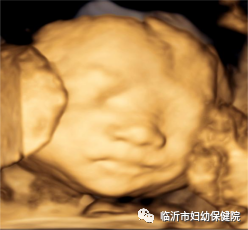

常规产前超声检查中医生问孕妈做大排畸了?“做了,在xxxx医院做的四维。”可想而知,很多很多的孕妈都把四维误认为是大排畸,认为维数越大,就越高级,非也非也。产前超声检查,包括“大排畸”是二维超声,三维、四维是在二维的基础上由计算机重建的,二维超声是平面成像,行外人士难于辨认,三维超声是立体成像,四维超声是三维超声的基础加上时间,即会动的三维,行外人士容易读懂。三维、四维超声图像是二维超声的一个辅助检查手段,对可疑异常建一步做出诊断。

#鼻唇部二维图像 >>

#鼻唇部三维图像 >>